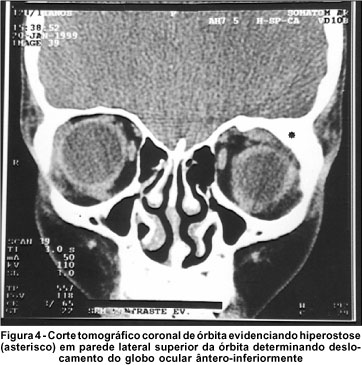

Foi solicitada TC de órbita que demonstrou presença de lesão hiperdensa em região superior da órbita, com hiperostose óssea e reação tissular circunjacente, causando proptose não axial e desviando o globo ocular para baixo e para fora.

O corpo estranho foi removido por via transpalpebral. No ato operatório foram encontrados três fragmentos de madeira medindo cerca de 32x15 mm, 19x10 mm e 15x7 mm.

Apesar da retirada dos fragmentos, não houve melhora de acuidade visual. O paciente ainda apresenta desvio do globo ocular, evidenciado clinicamente e ao exame de tomografia no pós-operatório (Figura 4). Será realizado novo procedimento cirúrgico para correção da hiperostose e reposicionamento do globo ocular.